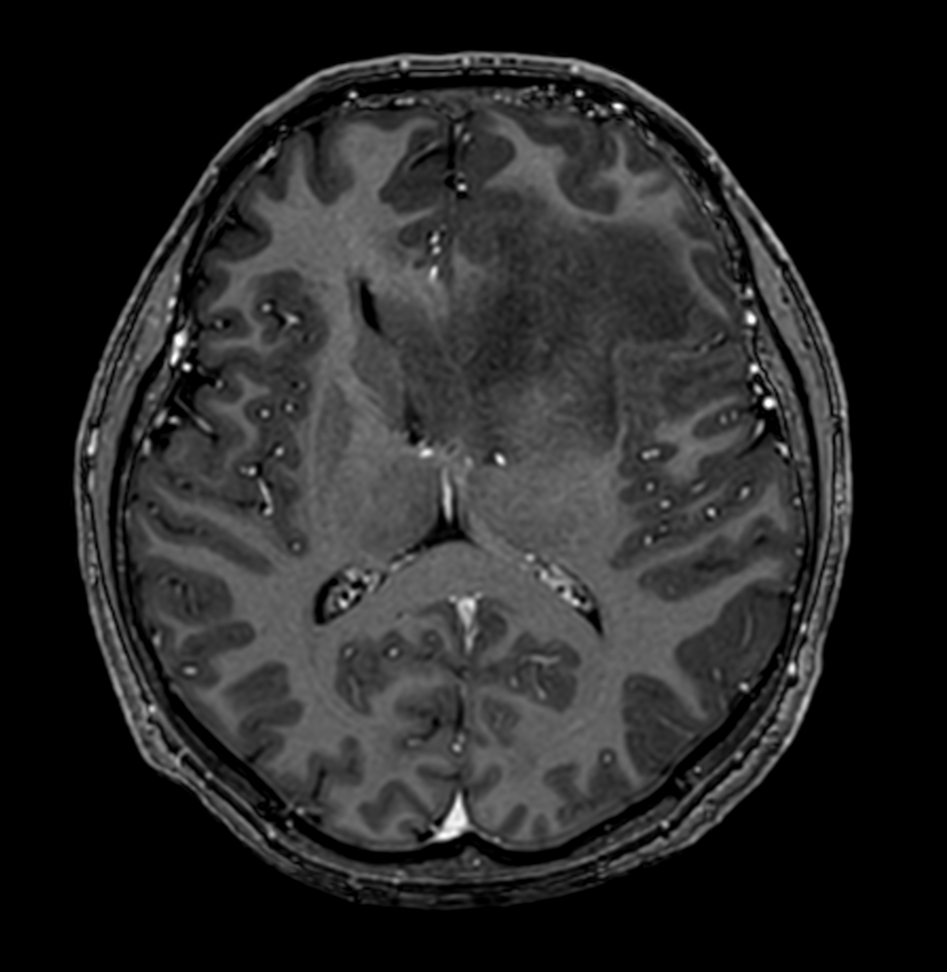

3D T1w TFE - Post-gado

3D T1w TFE - Post-gado (coronal reformat)

3D T1w TFE - Post-gado (sagittal reformat)